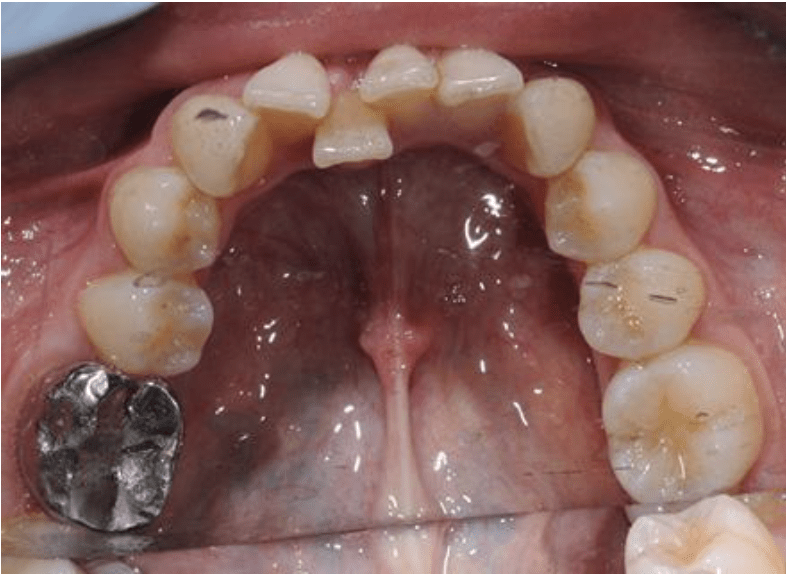

This case took under 12 months to straighten the very crooked teeth in the lower jaw and align the uppers as well. The finished photos show a fixed permanent wire on the inside of the teeth to stop them relapsing or moving back. Permanent wire retainers and night-time removable retainers are always recommended.